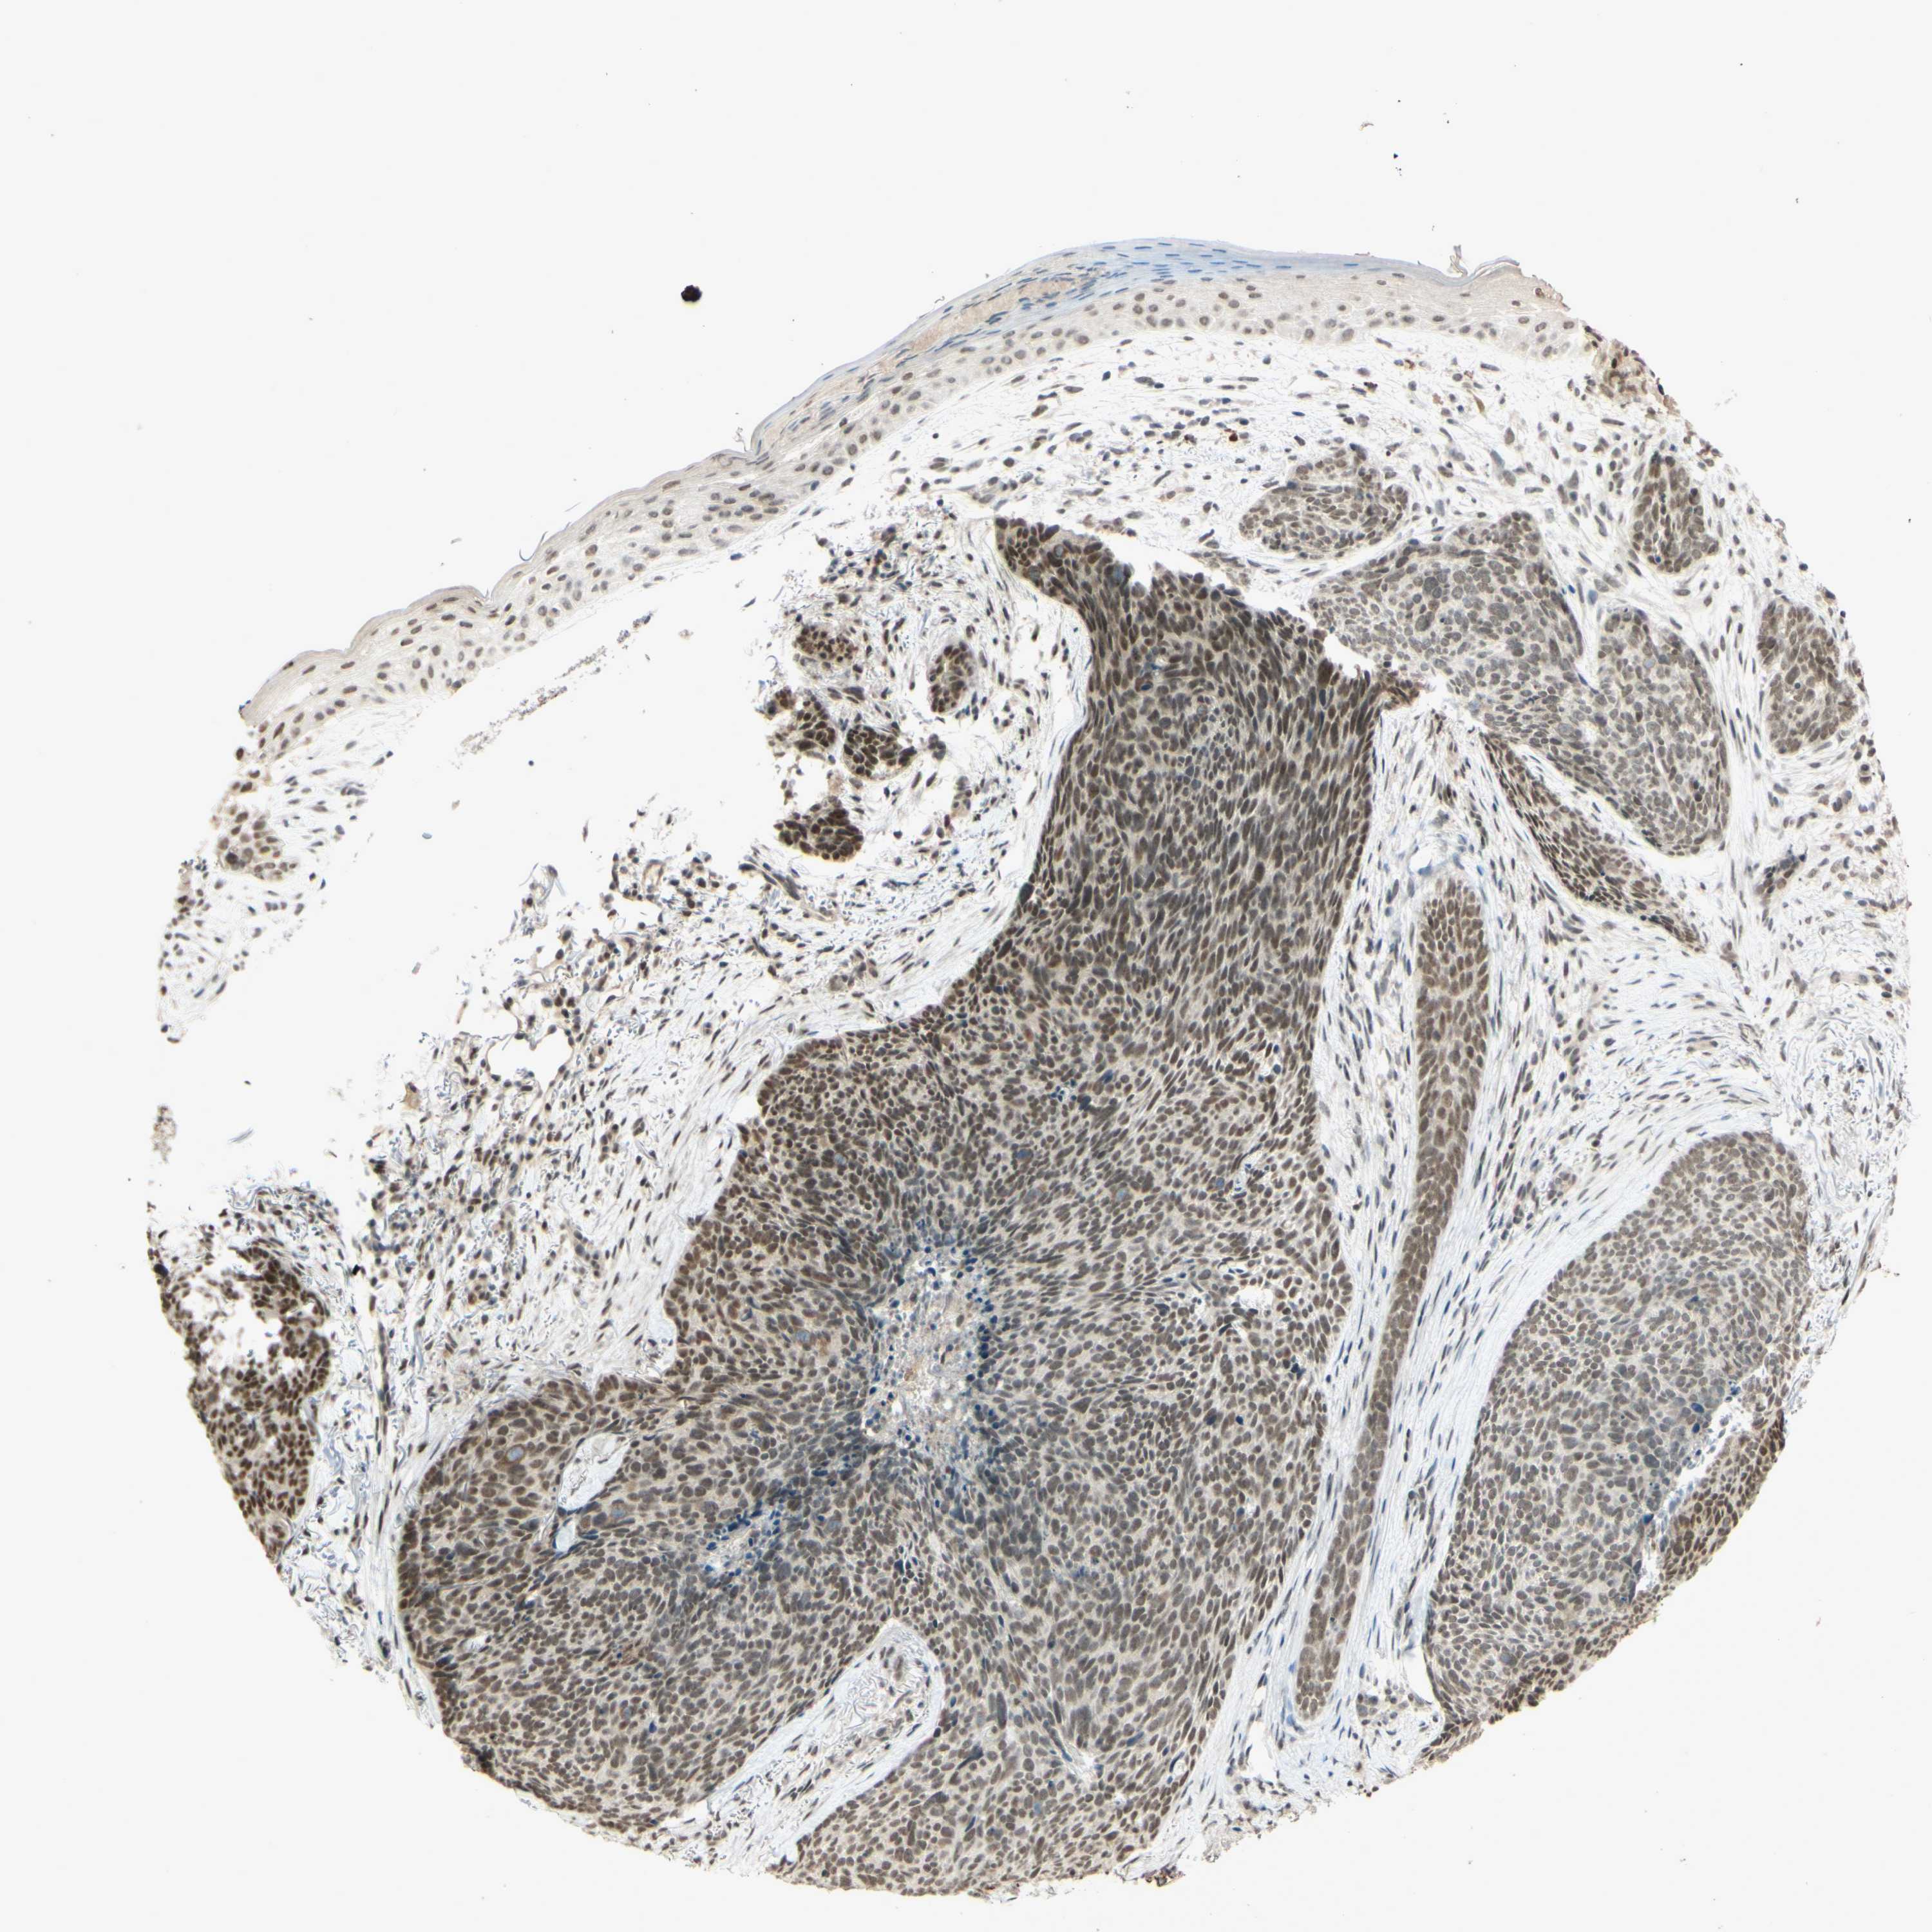

SKIN CANCER - Protein expressioni

A mouse-over function shows sample information and annotation data. Click on an image to view it in a full screen mode. Samples can be filtered based on level of antibody staining by selecting one or several of the following categories: high, medium, low and not detected. The assay and annotation is described here.

Antibody stainingi

Antibody staining in the annotated cell types in the current human tissue is reported as not detected, low, medium, or high, based on conventional immunohistochemistry profiling in selected tissues. This score is based on the combination of the staining intensity and fraction of stained cells.

Each image is clickable and will lead to virtual microscopy that enables deeper exploration of all samples and also displays staining intensity scores, fraction scores and subcellular localization as well as patient and tissue information for each sample.

Antibody HPA018248

Antibody HPA019127

Antibody CAB009196

Staining

High

Medium

Low

Not detected

Intensity

Strong

Moderate

Weak

Negative

Quantity

>75%

75%-25%

<25%

None

Location

Nuclear

Cytoplasmic/membranous

Cytoplasmic/membranous,nuclear

Squamous cell carcinoma in situ, NOS

Squamous cell carcinoma, NOS

Squamous cell carcinoma, metastatic, NOS

Basal cell carcinoma